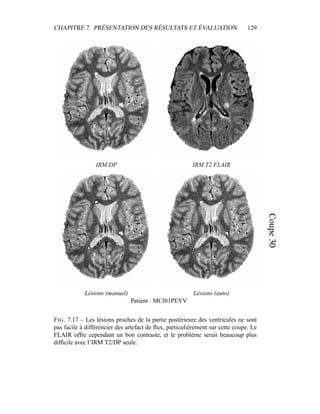

c’est donc sur elle que portera l’analyse lors de la segmentation en tissus et de la

présentation du modèle de volume partiel. Les autres modalités seront utilisées a

posteriori.

4.4 Segmentation en tissus.

4.4.1 Algorithme

Le but de cette segmentation en tissus sains est leur caractérisation, afin de

pouvoir construire un premier processus de détection des lésions de SEP. Même

si les 4 séquences (T2 FSE / DP, T1, T2 FLAIR) sont disponibles, la segmenta-

tion ne sera menée dans un premier temps que sur le couple T2/DP, alors que les

autres séquences – T1, T2 FLAIR – montreront tout leur intérêt pour la détection

des lésions et leur spécification : ceci permet de n’effectuer la segmentation que

sur des images vierges de tout rééchantillonnage. En outre, nous ferons délibéré-

ment l’impasse sur certains processus décrits dans la littérature pour améliorer la

qualité visuelle de la segmentation – les contraintes sur le voisinage, par exemple

– puisque notre but est d’obtenir un critère sur l’intensité qui sera raffiné ensuite

par contraintes spatiales.

Dans sa formulation la plus simple, le processus de segmentation prend un

ensemble multi-séquences à segmenter – les deux images T2 / densité de pro-

tons, auxquelles le masque binaire du cerveau a été appliqué – et fournit en sortie

3 labélisations : matière blanche, matière grise, LCR. Comme indiqué dans les

CHAPITRE 4. SEGMENTATION EN TISSUS 53

équations 4.10 et 4.11, l’algorithme EM donne deux grands résultats :

– la labélisation des segmentations via les γk

i

– l’estimation des paramètres du modèle µk et Σk.

4.4.2 Présentation des résultats

Pour éliminer dans un premier temps l’influence des lésions de SEP, un témoin

a été choisi pour cet exemple, et les résultats sont présentés dans la figure 4.5. Pour

la segmentation du masque du cerveau, seule la segmentation était intéressante.

Une mauvaise estimation des paramètres de classes, ou un mauvais modèle était

sans importance tant que la segmentation était valide. Par contre, dans le cas de la

segmentation en tissus, avoir une bonne estimation des paramètres est primordial,

car c’est à partir de là que les lésions de SEP vont être segmentées. Pour obser-

ver la qualité de la segmentation dans la figure 4.5, il faut donc en permanence

regarder deux espaces reliés.

– L’espace des intensités : visualisé via l’histogramme conjoint entre les deux

modalités, il est représenté par les paramètres de classes µk et Σk. Une mé-

thode pour visualiser ces paramètres est de tracer l’estimateur de confiance

donné par p(Z = z) = cte. Dans un espace 2D, cet estimateur est en fait

l’ellipse de Mahalanobis donné par 1

2

(X − µk)T

Σ−1

k (X − µk) = λ. Dans

toutes les figures similaires à la figure 4.5, les ellipses vérifieront λ = 1.

Pour avoir une meilleur visibilité de l’histogramme, celui-ci est en fait un

log-histogramme : la couleur de chaque pixel de l’image correspond au log

du nombre d’occurences du couple (IT2, IDP ) correspondant dans le couple

d’image IRM T2 / IRM DP. Ceci permet essentiellement de visualiser sur

le même histogramme le LCR avec le reste des tissus, bien que le nombre

de voxels correspondant au LCR soit très faible.

– L’espace des images, dans lequel les segmentations sont effectivement vi-